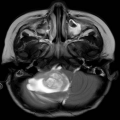

临床资料: 女, 2岁

患者详情: 主诉:行走不稳,饮水呛咳20余天 女童2岁2月,患儿于20天前无明显诱因出现行走不稳,持物不稳,饮水时出现呛咳,进食后呕吐,呕吐物为胃内容物,伴有头疼,无共济失调、视力减退,当地医院查头颅CT及MRI提示颅内占位,建议上级医院就诊。遂就诊于我院查头颅CT提示后颅窝占位并梗阻性脑积水,室旁脑白质水肿,MRI提示后颅窝右侧小脑延髓池及桥小脑脚区不规则囊实性肿瘤,病变与小脑半球及小脑蚓部部分界不清,病变内实性成份内可见弥散受限及增强,向下延伸至枕骨大孔水平以下10mm,脑干及小脑明显受压变形。 自发病以来,患儿精神、体力、食欲食量及睡眠情况无特殊。 既往史、个人史及家族史无特殊。

取材部位: 后颅窝占位

影像学检查:(点击查看大图)